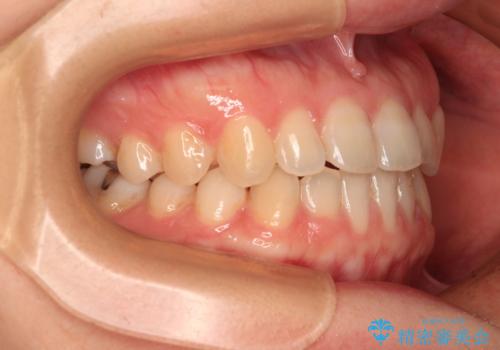

前歯のクロスバイト インビザラインによる矯正治療

インビザラインを用い、下顎歯列を後方に移動させながら全市の被蓋を改善し、歯並びを整えていくこととしました。

途中マウスピースが使用できず、来院されない期間があり、治療期間は長くかかりましたが、無事に治療を終えることができました。